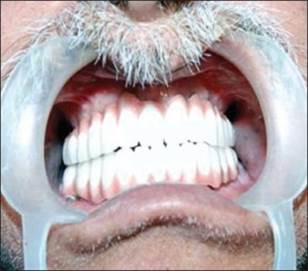

Un paciente de sexo masculino de 58 años había acudido al ala de pacientes externos de nuestro departamento, con una queja principal de falta de diente en los arcos maxilar y mandibular. El paciente quiere tener una prótesis fija ya que no estaba contento con la dentadura convencional [Figura 1] y [Figura 2] . Se registró un historial de casos adecuado para el paciente, incluido un historial médico que no era contributivo, con pruebas de laboratorio relevantes, exámenes dentales y orales. Se prepararon impresiones de diagnóstico y moldes. Se realizó un examen exhaustivo y el paciente estaba motivado para implantar prótesis. El mapeo óseo se realizó para evaluar el ancho del hueso, mediante el uso de ortopantamografía (OPG), se calculó la longitud del hueso disponible y se seleccionaron los implantes de tamaño apropiado [Figura 3]. Se preparó una plantilla quirúrgica para el maxilar y la mandíbula, y la posición de los implantes se decidió antes de la cirugía colocando un taladro en el implante.

Figura 1: Fotografía preoperatoria maxilar |

Figura 2: Fotografía preoperatoria mandibular |